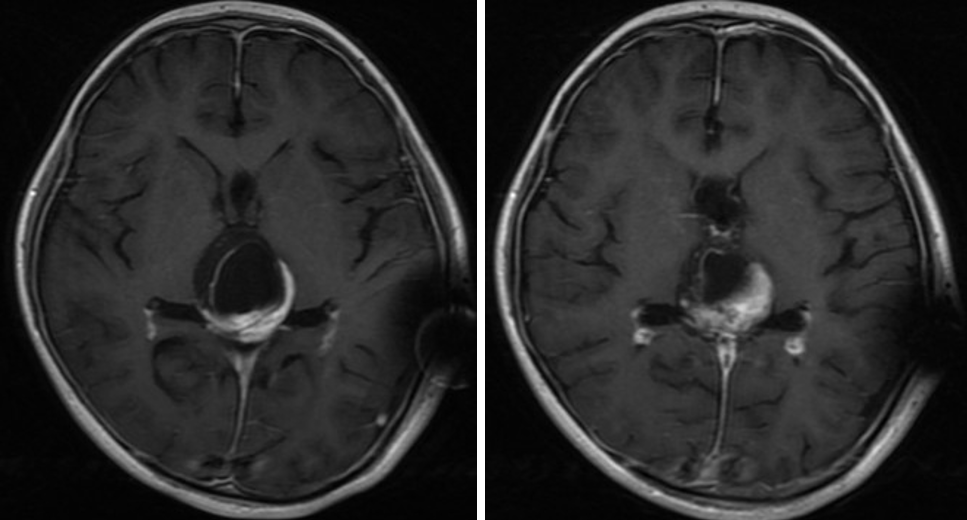

患者男性,4岁,患者因“间断恶心呕吐2月,加重伴精神萎靡1天。”为主诉急诊入院入院;查体:神志尚清,精神萎靡,眼球上视不能。外院CT提示松果体区占位,梗阻性脑积水,遂急诊行脑室腹腔分流术,术后精神状态好转,分流术后一周给予行内镜下肿瘤切除术。

我们在神经内镜下经幕下小脑上入路切除一例松果体区畸胎瘤,近年来神经内镜技术发展较快,内镜与显微镜一样,是神经外科医生手术的利器,尤其是年轻医生都应该积极学习掌握,当然也离不开老师们的带教和传承,该手术是在周文科教授和王仲伟教授的指导下完成,在此表示感谢。